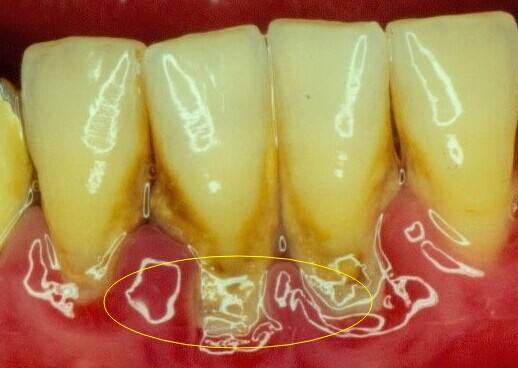

洗牙之后牙縫會變大嗎?實際上這個是犯了邏輯錯誤問題。不是洗牙導致牙縫變大的,而是洗牙時把牙縫中的牙結石去掉了,因此你感覺牙縫中變空變大了,這是因為牙縫本來就被牙結石占據導致變大的。

本來我們的牙齒牙縫是很小的,牙齒都緊挨著,但是慢慢地,因為有時一些食物殘渣殘藏在牙縫中,刷牙也難以全方位、無縫隙的清除到位,久而久之形成了牙結石,而當我們把這些牙結石去掉之后,原本牙結石的位置空了,就會顯得牙縫特別大。

這個感覺其實是跟有牙結石的時候對比的感受,但你想過嗎?有的牙結石是很大的一片,去掉后肯定十分明顯是會感覺到空的,但大概兩周左右就不會再有那種“牙縫特別大”的感覺了,大概是習慣了吧。

其實,洗牙的好處就是把你牙縫中的牙結石清除干凈,預防口腔疾病,而牙結石,通常是很硬的,一旦形成,即使你刷牙也刷不掉。